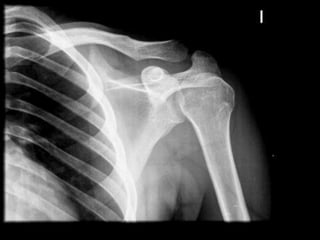

ARTICULACION GLENOHUMERAL

Capsula y ligamentos del la articulación glenohumeral

Movimientos de la articulacionglenohumeral

Luxacion la articulacionglenohumeralARTICULACION DEL CODO